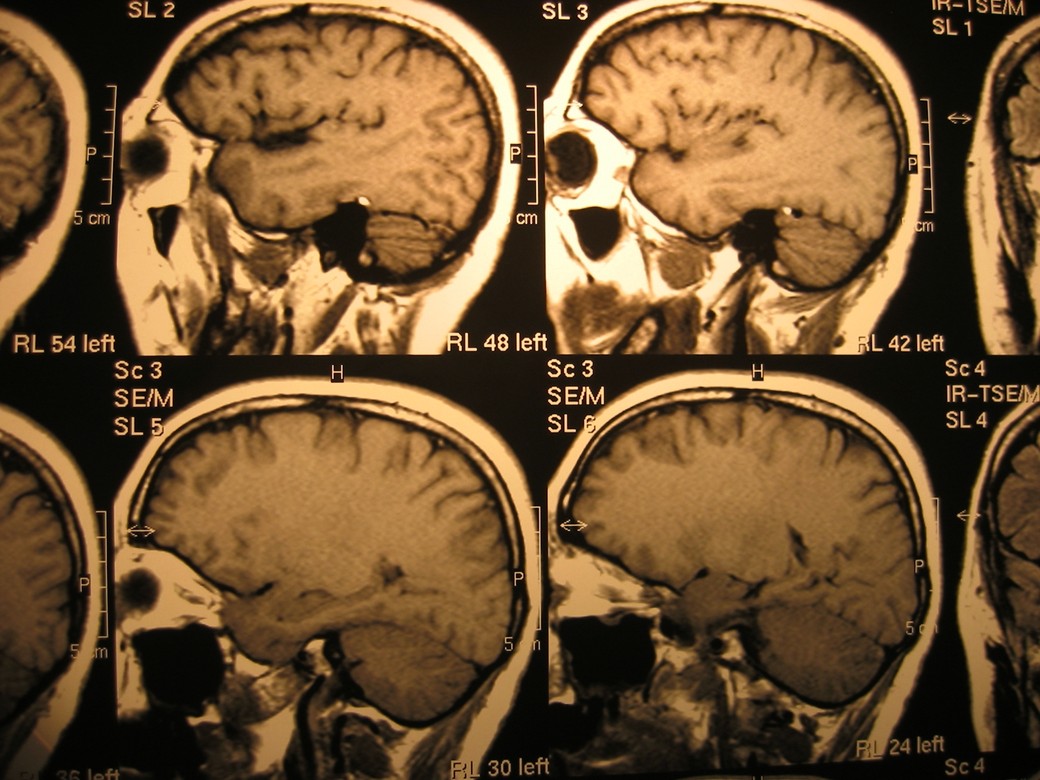

Progenics Cord Blood Cryobank aims to cure and treat diseases